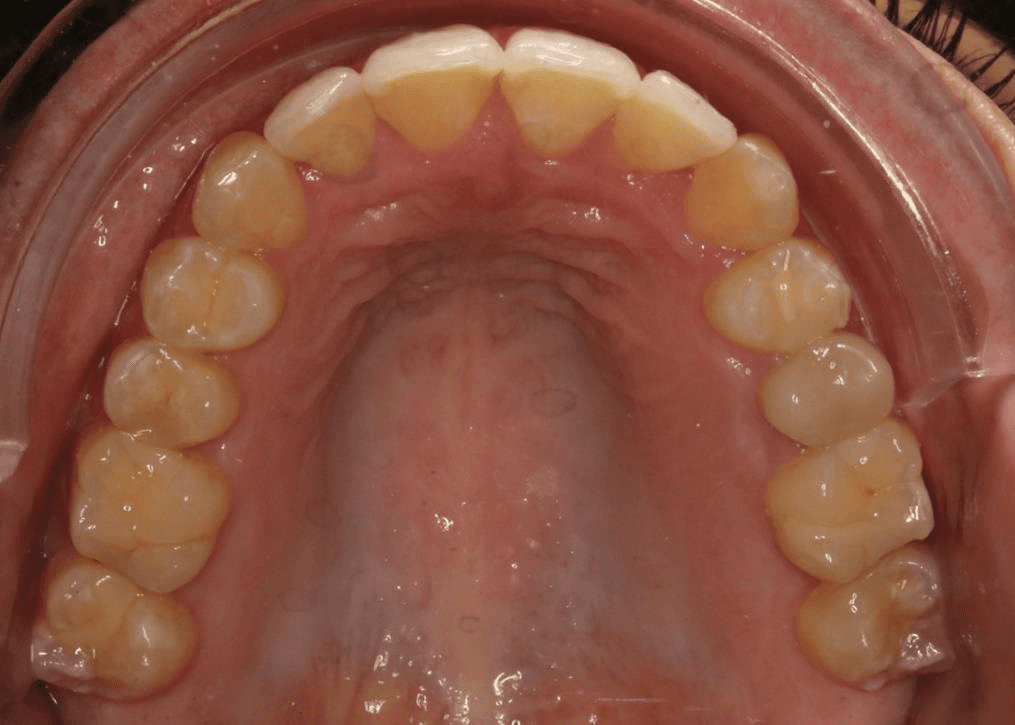

Final results

INTRAORAL

Diganosis: Moderate crowding in both arches, constricted arch forms with anterior and posterior single tooth crossbites, poor smile display